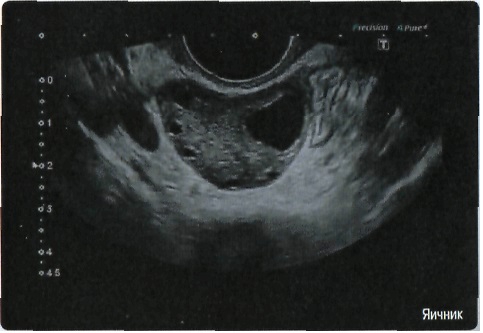

• Превосходное качество визуализации и детализации анатомических структур для широкого спектра областей использования.

Общая визуализация, Гинекология и акушерство, УЗИ для кардиологии

Гинекология:

Да